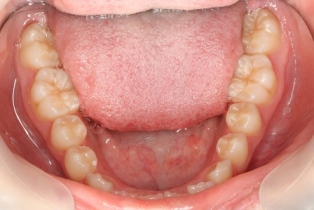

14歳の妹さんです。お姉さんと同じく園児の時からメインテナンスに来ています。これこそが歯科医療のゴールであり、患者さんと術者の win-win の関係ではないでしょうか。健康なのですが健康維持のためのメインテナンスです。